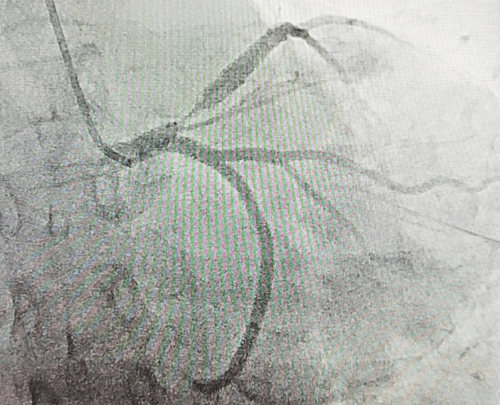

右側(cè)子宮動(dòng)脈栓塞前后對(duì)照

子宮動(dòng)脈栓塞術(shù)屬于血管介入性治療,方法是于股動(dòng)脈穿刺進(jìn)針插入導(dǎo)管,在X射線造影下定位進(jìn)入兩側(cè)子宮動(dòng)脈,注入栓塞劑完全栓塞子宮動(dòng)脈,從而達(dá)到止血或讓子宮肌瘤和病灶缺血壞死的目的;2022年12月6日,在崔旭輝主任、孟慶槐副主任醫(yī)師、馬力主治醫(yī)師等我院介入團(tuán)隊(duì)協(xié)作下,成功為患者進(jìn)行了雙側(cè)子宮動(dòng)脈栓塞術(shù),術(shù)后患者子宮異常出血停止,效果立竿見影,患者病情恢復(fù)良好。